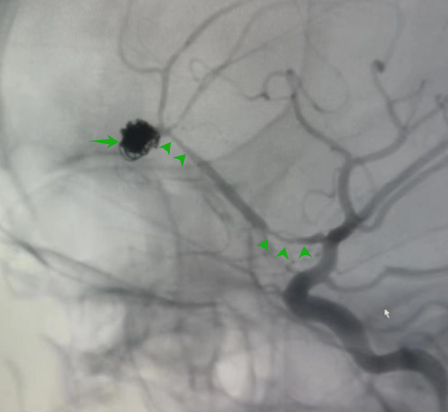

▲弹簧圈致密填塞呈现完整瘤体形态

微导管精准到位后予使用弹簧圈小心填塞,达到致密栓塞(Raymond1级),填塞后可见完整瘤体形态。近端多处狭窄为血管痉挛,可用药物治疗后改善。术后患者无不适,恢复迅速,目前已步行出院。